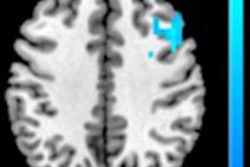

Danish researchers identified areas of heightened brain activity in people who celebrate Christmas, compared with those who have neutral feelings. All images courtesy of BMJ.MR images were obtained on a 3-tesla scanner (Achieva, Philips Healthcare), with T1-weighted magnetization-prepared rapid gradient-echo (MPRAGE) imaging for anatomical reference. Functional MRI scans used an echo-planar imaging sequence, along with cerebral perfusion through an arterial spin-labeling (ASL) sequence.

Baseline perfusion scans recorded normal results for all subjects and no significant differences between the two groups (p = 0.26). Both groups also reacted with increased brain activity in the primary visual cortex when shown Christmas images versus everyday scenes (p < 0.001).

However, fMRI detected significant increases in neural activations in the primary somatosensory cortex of subjects in the Christmas group when they viewed a holiday theme.

In fact, fMRI activation maps reflected five areas of heightened activity in response to holiday images in the Christmas group versus the non-Christmas group. These areas were the left primary motor and premotor cortex, right inferior and superior parietal lobule, and bilateral primary somatosensory cortex (p < 0.001).